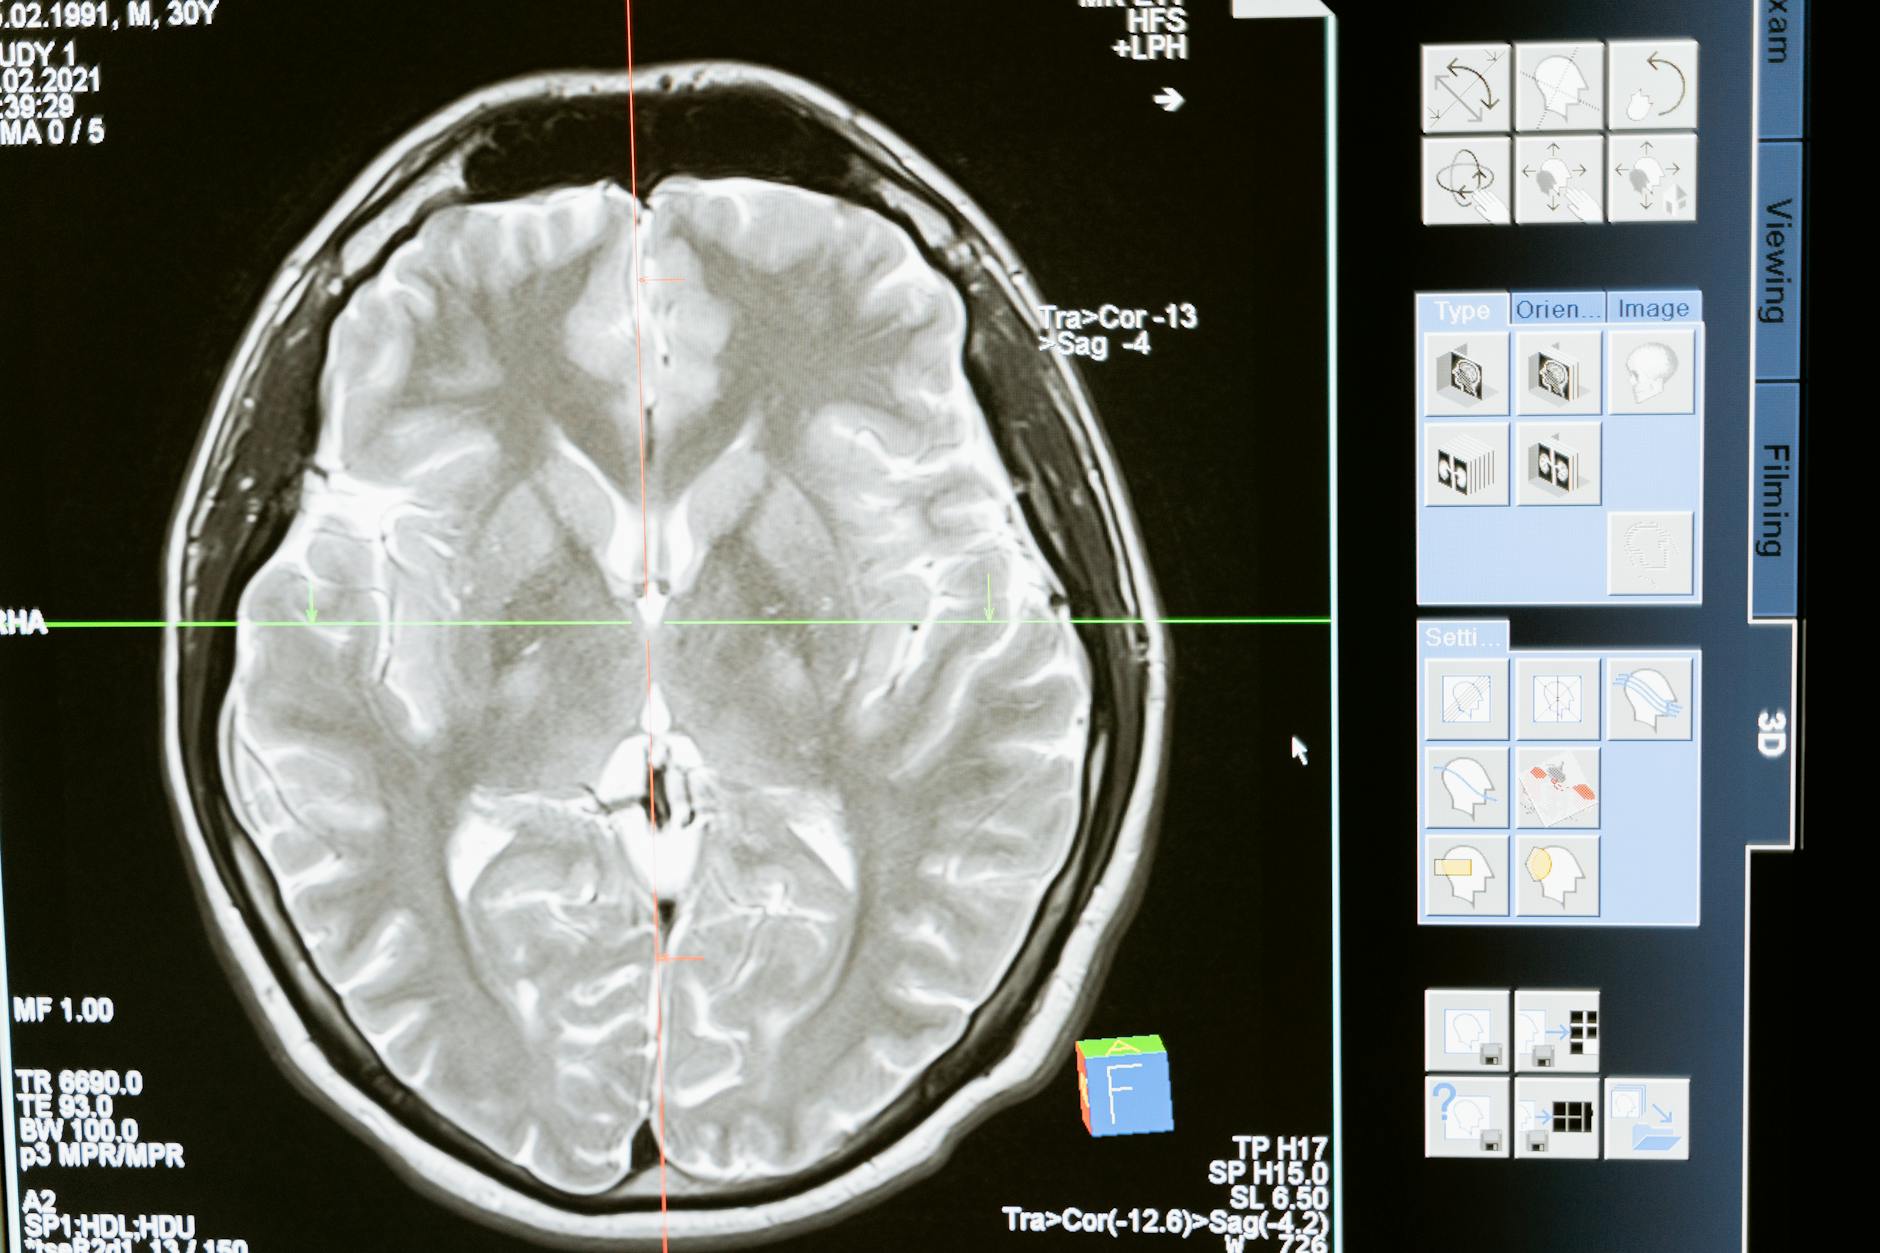

– 기존의 뇌전증 진단은 EEG(뇌파 측정)에 의존하며, 장기 모니터링 환자의 경우 전문가가 영상 데이터를 수 시간 동안 수작업 분석해야 함

○ 이에 따라 덴마크의 EPIFY 프로젝트는 실시간 뇌파 패턴을 자동 인식하고 발작 발생 시점 알림 기능을 갖춘 고정밀 마이크로칩(System-on-Chip)을 개발 중

○ 개발 중인 마이크로칩은 딥러닝 기반 신경망 알고리즘과 고효율 칩 기술을 통합하여 발작 신호를 자동으로 탐지·분류하고 진단 정확도 향상 및 병원 진단 인력 부담을 완화하는 것을 목표로 함